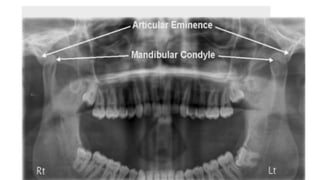

• Investigations• Orthopantomogram (OPG) (open and closed) This is the

shows the position of the condyle in relation to the articular eminence.•